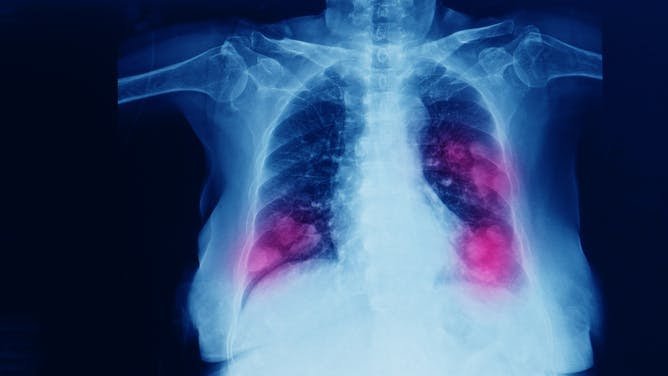

El paso del tiempo lo cambia casi todo menos la principal causa de cáncer en el mundo, que en las últimas décadas ha sido el cáncer de pulmón. Solo en España se diagnostican más de 30 000 casos cada año, y la supervivencia a cinco años apenas alcanza el 20 %. Parte del problema es que los tumores suelen detectarse tarde y que los tratamientos, incluso los más novedosos, acaban perdiendo eficacia.